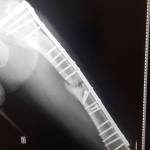

BAUCERO SE RECUPERA DE LA OPERACIÓN

El senador por el departamento San Javier, se recupera satisfactoriamente de la intervención quirúrgica a la que fue sometido hace algunas semanas, así lo confirmó el Dr. Víctor Abraham.